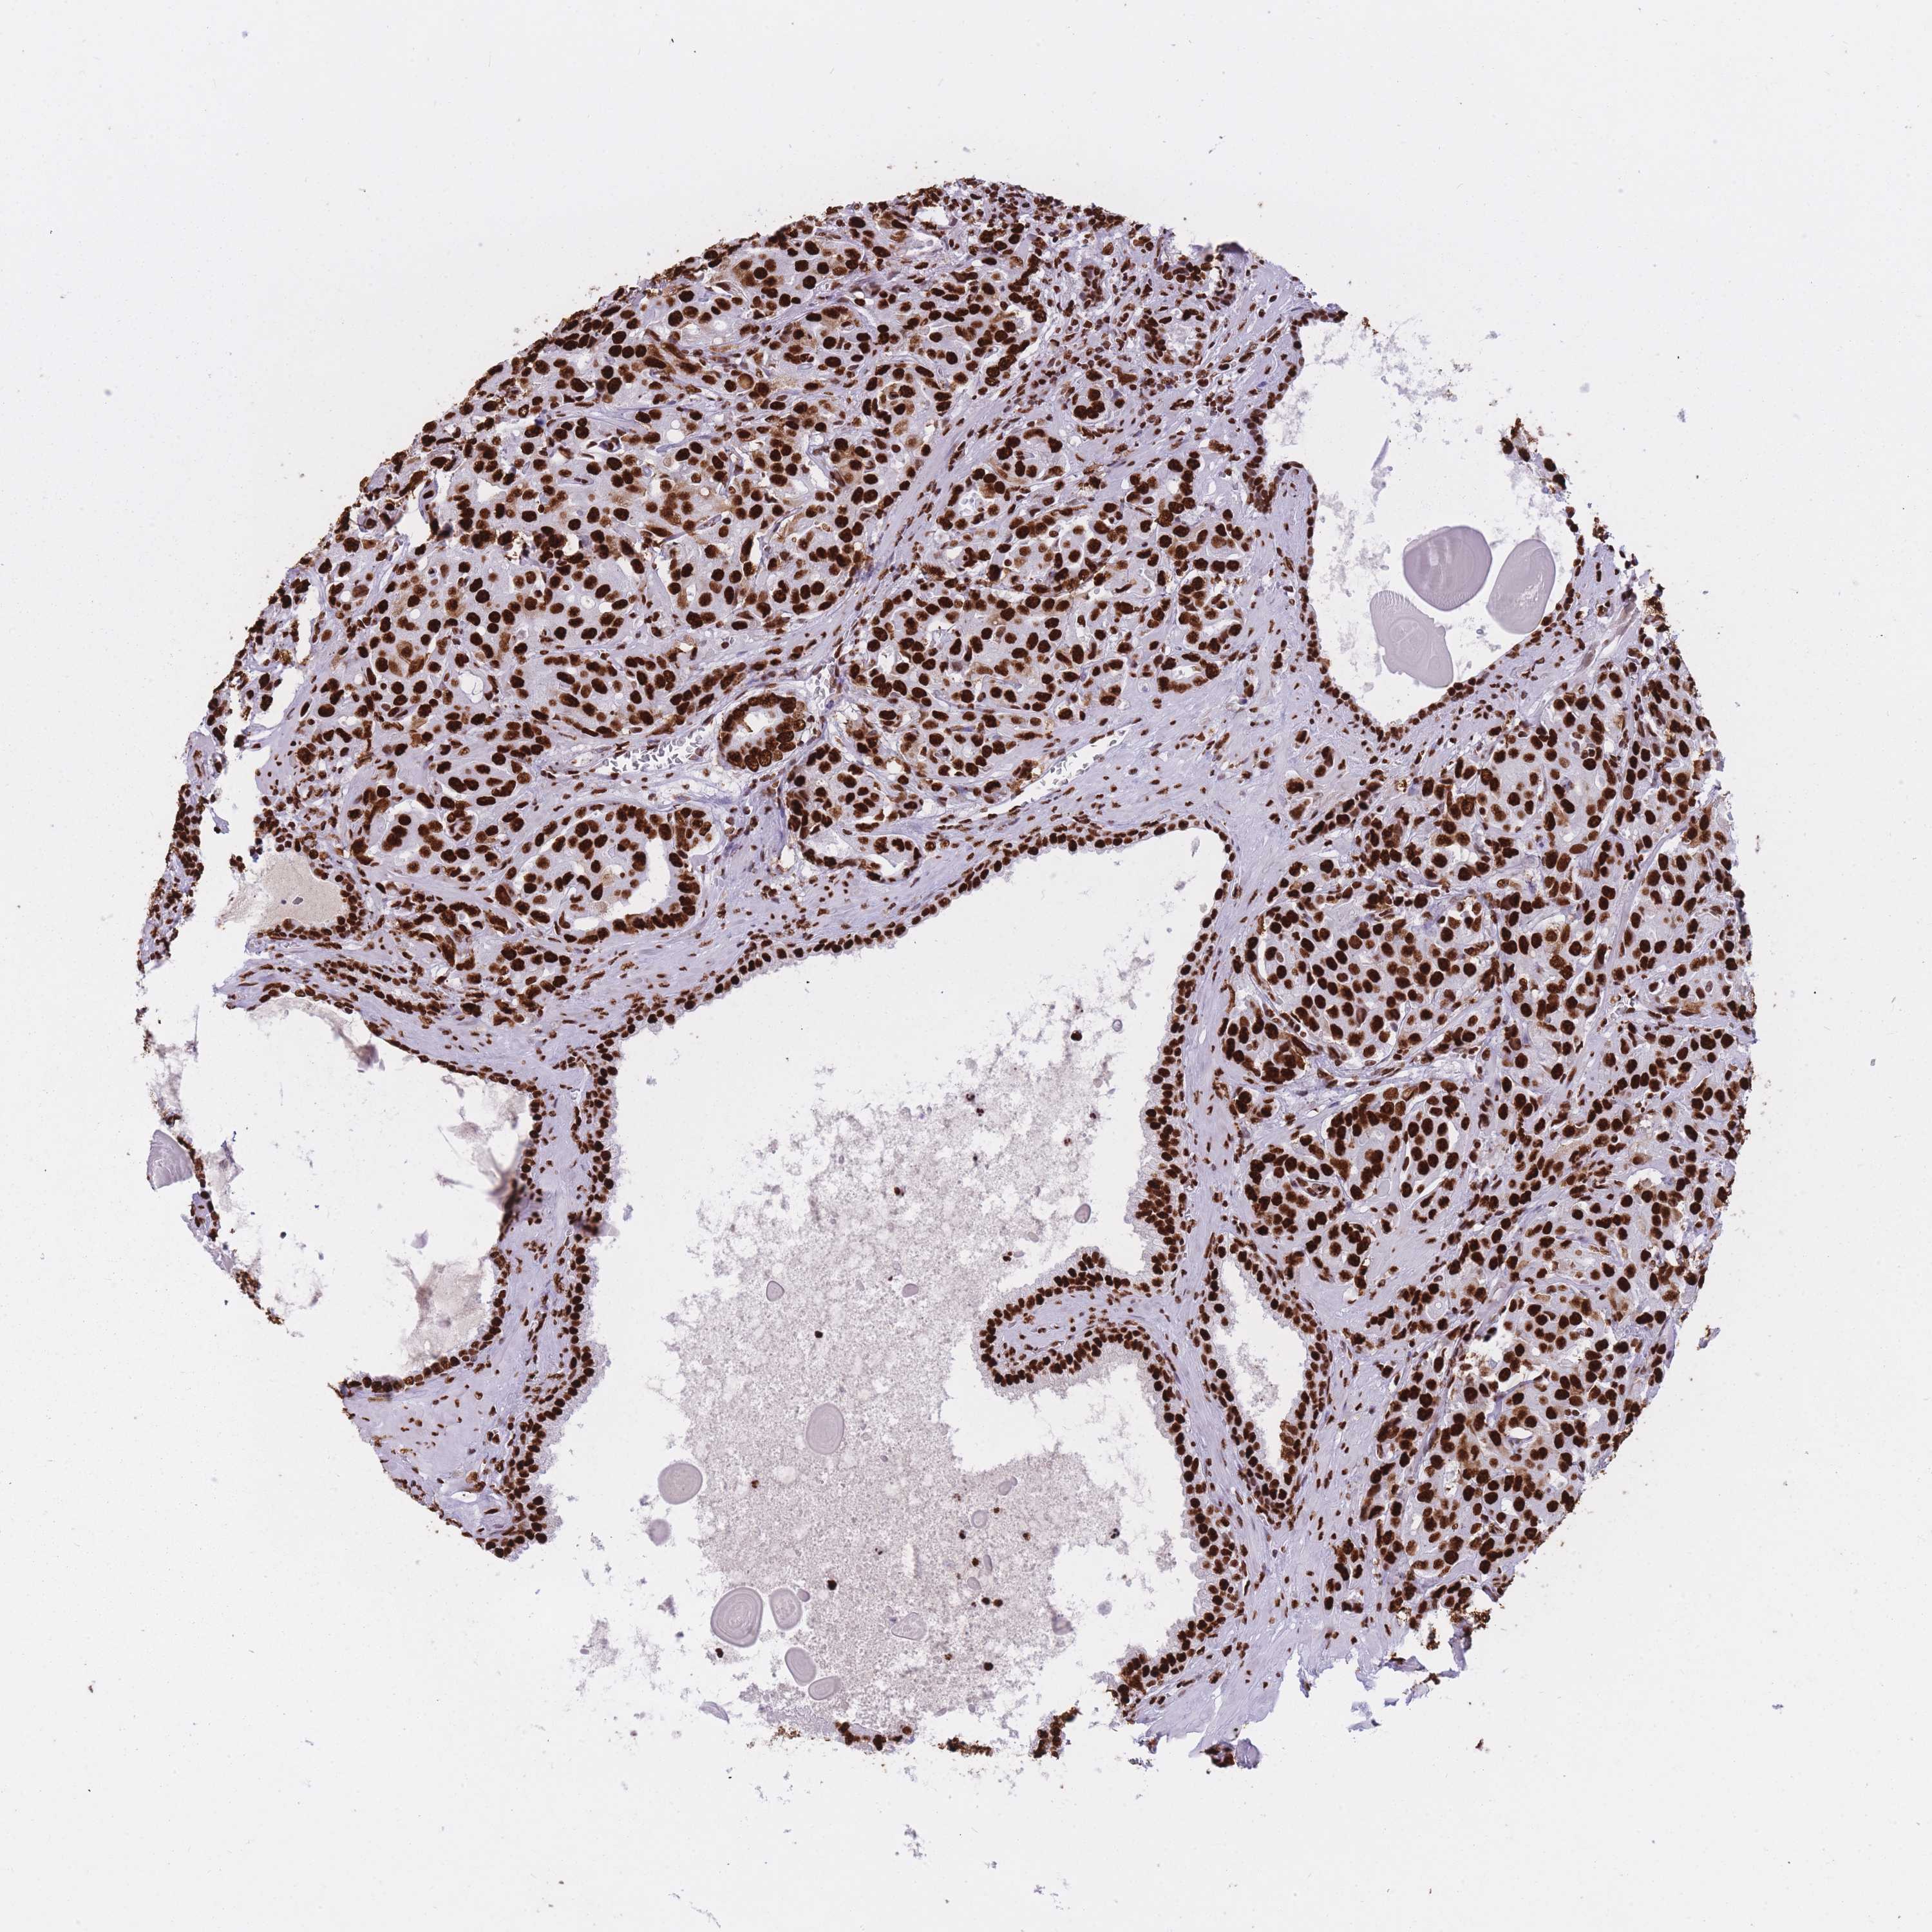

PROSTATE CANCER - Protein expressioni

A mouse-over function shows sample information and annotation data. Click on an image to view it in a full screen mode. Samples can be filtered based on level of antibody staining by selecting one or several of the following categories: high, medium, low and not detected. The assay and annotation is described here.

Antibody stainingi

Antibody staining in the annotated cell types in the current human tissue is reported as not detected, low, medium, or high, based on conventional immunohistochemistry profiling in selected tissues. This score is based on the combination of the staining intensity and fraction of stained cells.

Each image is clickable and will lead to virtual microscopy that enables deeper exploration of all samples and also displays staining intensity scores, fraction scores and subcellular localization as well as patient and tissue information for each sample.

Antibody CAB046477

Staining

High

Intensity

Strong

Quantity

>75%

Location

Nuclear

Adenocarcinoma, High grade

Adenocarcinoma, Low grade